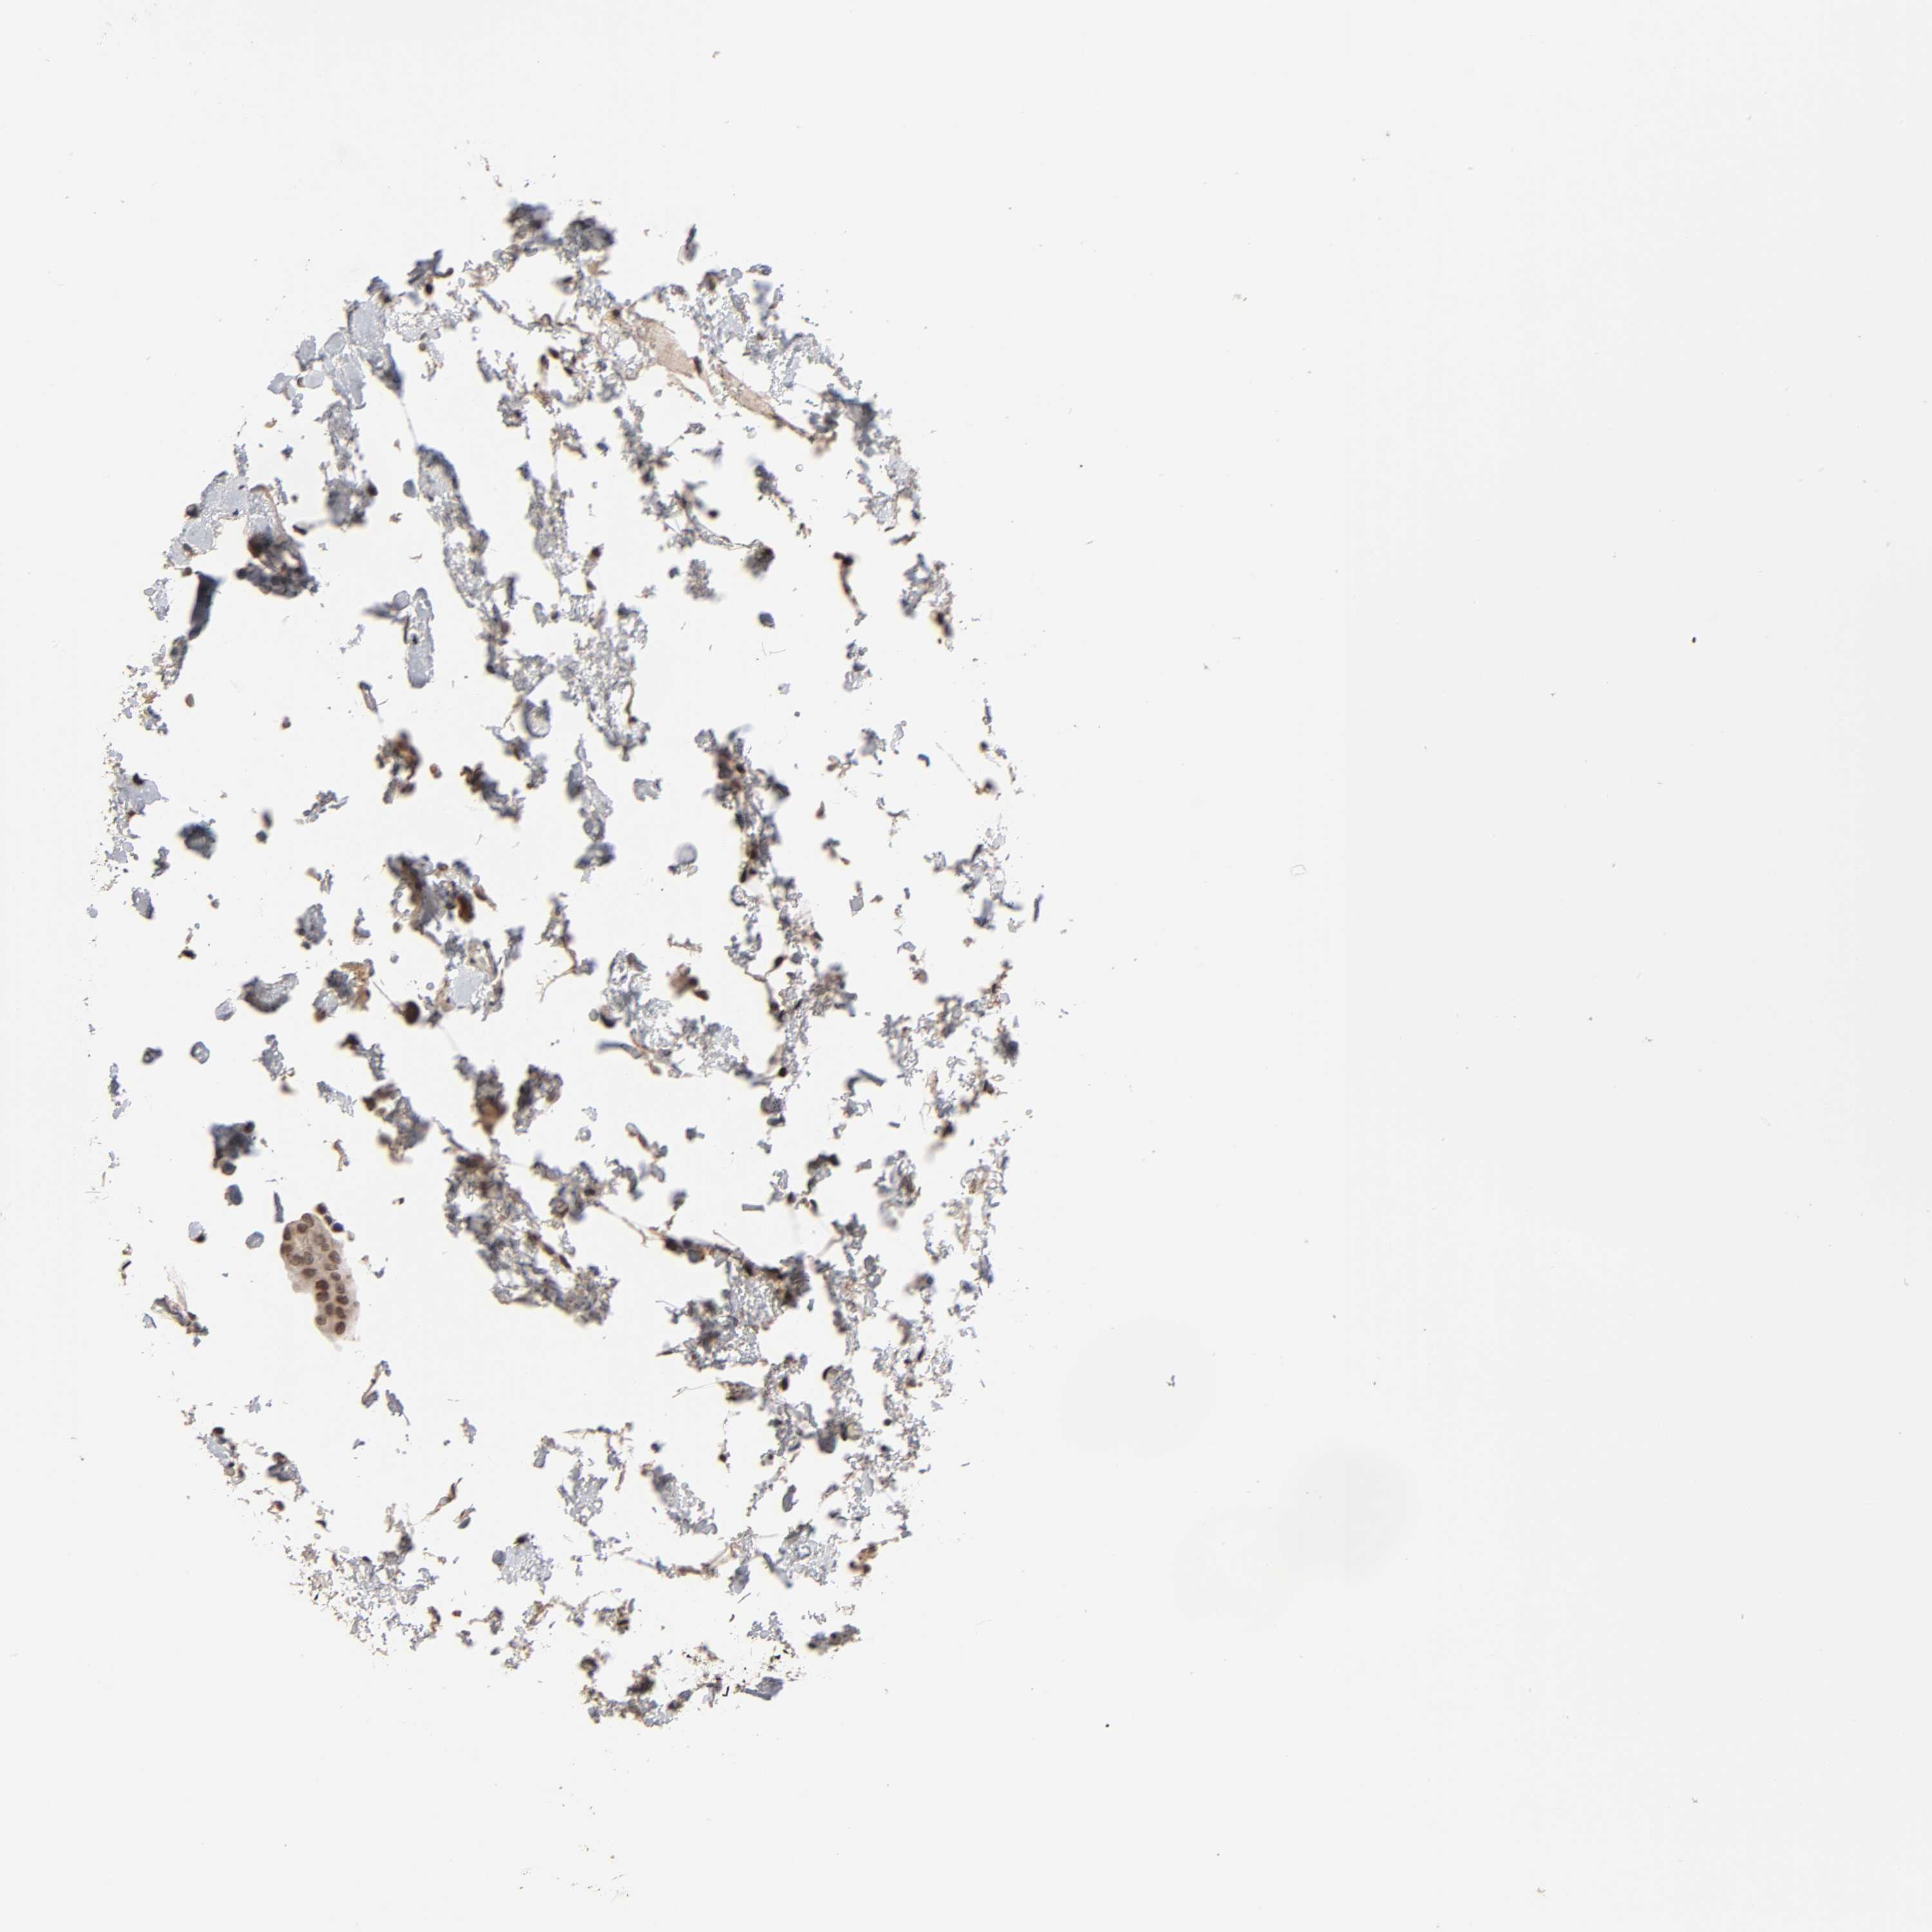

UROTHELIAL CANCER - Protein expressioni

A mouse-over function shows sample information and annotation data. Click on an image to view it in a full screen mode. Samples can be filtered based on level of antibody staining by selecting one or several of the following categories: high, medium, low and not detected. The assay and annotation is described here.

Note that samples used for immunohistochemistry by the Human Protein Atlas do not correspond to samples in the TCGA dataset.

Antibody stainingi

Antibody staining in the annotated cell types in the current human tissue is reported as not detected, low, medium, or high, based on conventional immunohistochemistry profiling in selected tissues. This score is based on the combination of the staining intensity and fraction of stained cells.

Each image is clickable and will lead to virtual microscopy that enables deeper exploration of all samples and also displays staining intensity scores, fraction scores and subcellular localization as well as patient and tissue information for each sample.

Antibody HPA004732

Staining

High

Medium

Low

Not detected

Intensity

Strong

Moderate

Weak

Negative

Quantity

>75%

75%-25%

<25%

None

Location

Nuclear

Cytoplasmic/membranous

Cytoplasmic/membranous,nuclear

Urothelial carcinoma, High grade

Urothelial carcinoma, Low grade